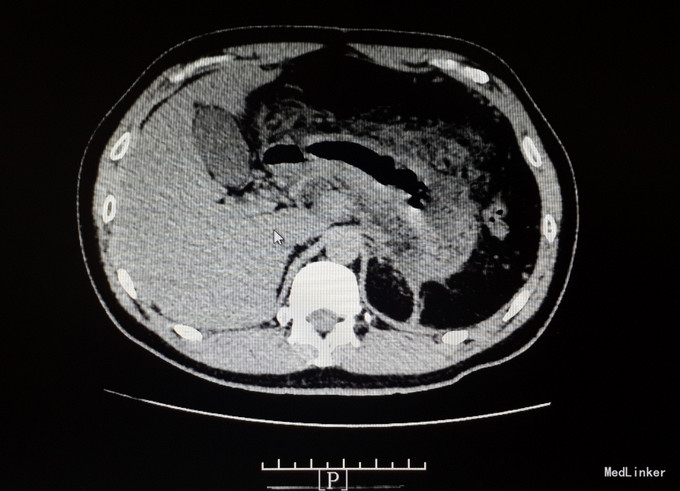

查体:体温:36.8℃(X),血压:130/80mmHg,神清,精神状态可,皮肤及巩膜无黄染,双肺呼吸音清,未及啰音,心率:80次/分,律齐,未及杂音,全腹平软,见陈旧性手术疤痕,全腹压痛,上腹明显,无反跳痛,未及包块,肝脾肋下未及,Murphy征阴性,麦氏点无压痛,肝浊音界存在,肝肾区无叩痛,肠鸣音为4次/分,双下肢不肿。 入院查: 淀粉酶 285.000(U/L)↑,脂肪酶 148.000(U/L)↑; 全血常规五分类:中性粒细胞计数 14.360(10E9/L)↑,白细胞计数 16.520(10E9/L)↑,血红蛋白浓度 176.000(g/L)↑,淋巴细胞比例 0.072↓,红细胞压积 0.502↑,中性粒细胞比例 0.869↑; 感染三项:降钙素原 0.994(ng/ml)↑,白细胞介素-6 52.420(pg/ml)↑,超敏C反应蛋白 212.000(mg/L)↑; 空腹血糖:葡萄糖 8.430(mmol/L)↑; 肾功正常, 肝功能八项:总胆红素 18.100(umol/L),白蛋白 44.000(g/L),直接胆红素 3.200(umol/L),亮氨酰氨基肽酶 34.300(U/L),γ-谷氨酰转肽酶 39.000(U/L),丙氨酸氨基转移酶 21.000(U/L);白、球蛋白比例 1.000↓,球蛋白 46.000(g/L)↑,总蛋白 90.000(g/L)↑,间接胆红素 14.900(umol/l)↑,门冬氨酸氨基转移酶 42.000(U/L)↑; 电解质六项:镁 0.800(mmol/L),钙 2.370(mmol/L),钾 4.170(mmol/L),钠 138.500(mmol/L); 血脂全套(分型+载脂蛋白):总胆固醇/高密度 7.400↑,总胆固醇 8.440(mmol/L)↑,游离脂肪酸 0.830(mmol/L)↑,极低密度脂蛋白 5.680(mmol/L)↑,低密度脂蛋白 1.620(mmol/L)↑,甘油三酯 13.550(mmol/L)↑。 全腹增强CT ,1、考虑:急性坏死性胰腺炎伴胰腺周围局部肠管郁张(炎症具体波及范围如上所述)。 2、考虑:脂肪肝,左肾小结石,脾脏术后缺如。 ((具体描述:胰腺尾部结构不清,胰腺余部体积明显增粗,边缘毛糙、不整,其内密度不匀并可爱可见散在多分小点状钙化影,增强不均匀明显强化,其内可见多发斑片状无强化的坏死区,小网膜囊等胰周、胃周间隙内见大量规则斑片状、片絮、条状密度增高影,增强后轻度强化,两侧肾前筋膜增厚、密度增高,增强后轻度均匀性强化,相邻小肠管轻度扩张,管壁轻度增厚强化,管腔内可见多发气液平征象。)

诊断:1.急性坏死性胰腺炎,2.高脂血症, 入院后予以禁食、抑酸、抗感染、改善胰腺微循环、降血脂、护肝等对症治疗,1周后患者腹痛逐步缓解,肛门恢复排气排便,复查淀粉酶等血生化均正常,复查腹部CT示:胰腺边缘较前清晰。左侧肾上腺略肥大,边缘模糊,考虑炎症累及所致可能性大,现强化较前减轻,余大致同前。2、脂肪肝,左肾小结石,脾脏术后缺如。大致同前。